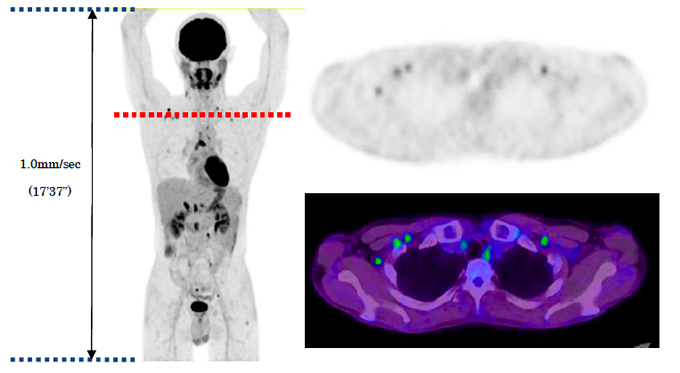

悪性リンパ腫患者のPET像(左),PET横断像(右上),PETとCTの融合像(右下)

PETとCTの融合像を用いることによってより正確な病変の位置情報が得られます。PET-CTにより一度の検査で、この融合画像を取得できます。